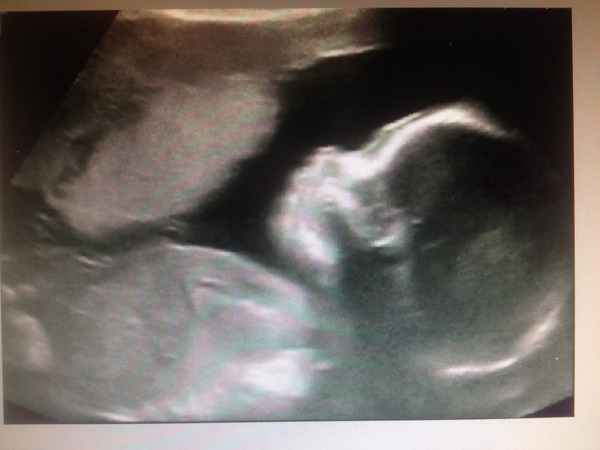

Had my scan, baby all healthy and good, though somewhat acrobatic! It had its foot on its forehead at first and wriggled around like crazy! So much so I have to go back in a couple of weeks for another scan as she couldn't get one of the heart measurements, she said nothing's wrong, it's just one of the hardest measurements to get, especially on an acrobat Grin as for flavour, same applies on the wriggle front but she said she didn't see any obvious man junk, so 'probably a girl' so I'll get them to have another little peep at my bonus scan.

Pics a bit weird, just took it off the PC screen at home as DH is scanning them all in now!